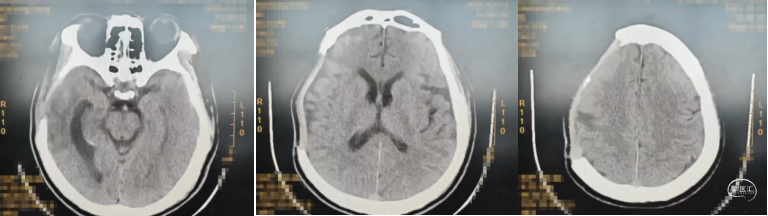

诊疗过程:急诊行开颅硬膜下血肿清除+脑挫裂伤病灶清除+去颅骨骨瓣减压,术后20天意识逐步转清,病情平稳后转康复科康复,术后两个半月再次住院行颅骨修补,患者意识清,言语清晰,肌力正常,骨窗略凹陷,切口愈合良好,术中行peek板修补,完整暴露骨窗缘,充分止血,将已塑形好颅骨固定系统1个(天津市康尔医疗器械有限公司;颅骨固定系统)及内固定板5个(天津市康尔医疗器械有限公司;聚醚醚酮颅骨内固定板)安放满意,脑组织未受压,以颅骨螺钉(天津市康尔医疗器械有限公司;颅骨螺钉)10枚,沿骨缘将颅骨固定系统固定于骨质上,确认固定牢靠外形满意,与骨窗贴合紧密无移位,术中行硬膜悬吊于peek板孔隙,皮下硅球引流,弹力绷带加压包扎,48小时后拔除引流管。

颅骨修补术后CT: